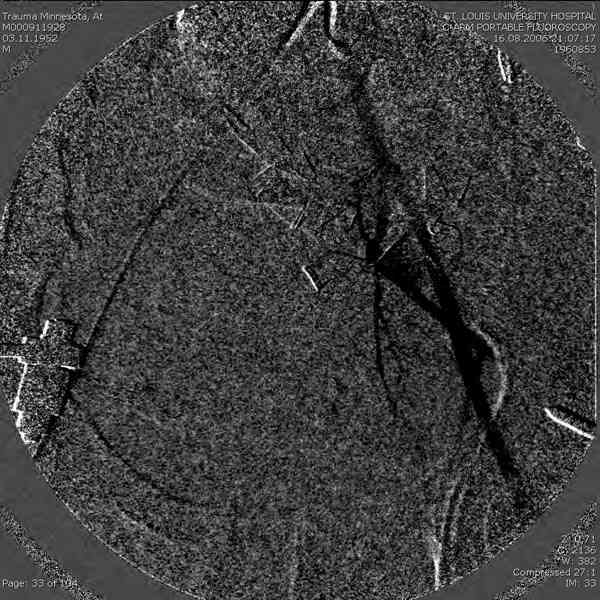

Прооперировали молодую девушку 32 лет спустя 9 мес после травмы. Имелся стойкий болевой синдром, неопороспособность левой н/конечности, моторные и сенсорные нарушения в левой голени и стопе, патологическая подвижность левой половины таза. Первым этапом закрыто в аппарате исправили деформацию ( в течении 2,5 нед). Вторым закрытое введение илиосакральных винтов в крестец (канюллированные 7,2 мм Chm) + туннелизация зоны псевдоартроза спицама Киршнера, реконструкция передних отделов таза, накостный остеосинтез . Аппарат частично демонтирпован, оставлена "передняя рама" После устранения деформации отмечен регресс неврологической симптоматики, уменьшение болевого синдрома. Интересующие вопросы: 1. Прогноз для сращения псевдоартроза крестца. 2. сроки нагрузки весом левой половины таза. Буду очень признателен за ваши мнения по этому поводу.A female 32 y.o. admitted to our unit 9 months after initial injury with pain, inability to bear weight at the left lower limb, sensor and motor disturbances in the left foot and tibia, with mobility of the left hemipelvis.At first closed reduction was performed by an external fixator within 2,5 weeks. After correction her pain decreased and some neurological progress was achieved. Now two iliosacral screws 7,2 mm were inserted, and anterior lesion was fixed by a plate. External fixator was partially unmounted, only anterior frame left in place.Images attached.How would you evaluate chances of healing of the sacrum with the current position?When would you allow weight-bearing of the left leg?THX in advance.

Мне нравится ваша закрытая репозиция девятимесячного ложного сустава, не знаю насчет туннелизации, но шурупы в 7.2 это серёзная конструкция. При стабильной фиксации крестец должен срастись, только я бы держал передний фиксатор до шести недель, костыли, а полную нагрузку разрешить через 12 недель.